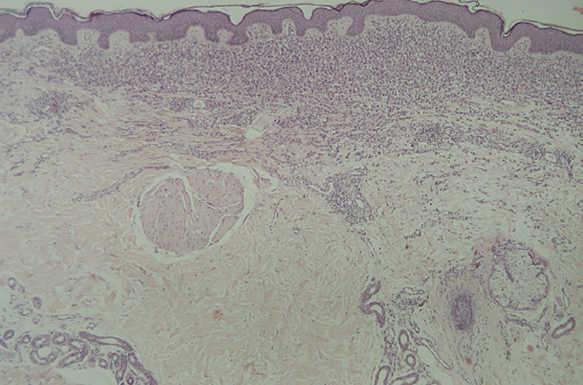

En la HCL el infiltrado se localiza normalmente en la dermis adventicial, y puede invadir la epidermis, produciendo clínicamente lesiones erosivas (figs. 13 y 14). En las formas nodulares puede invadir la hipodermis. En pacientes adultos se ha descrito la distribución del infiltrado alrededor de los anejos (figs. 15 y 16) 13. Aparecen otras células inflamatorias en número variable, sobre todo neutrófilos, eosinófilos, linfocitos y mastocitos y, en menor medida, células gigantes multinucleadas. De forma clásica se han descrito tres subtipos principales: proliferativo, granulomatoso y xantomatoso, que se intentan correlacionar con las diferentes formas clínicas. Histológicamente no existen diferencias entre la HCL y la reticulohistiocitosis congénita autoinvolutiva 7.

Fig. 13.--Infiltrado en placa subepidérmico conformado por células de Langerhans. (Hematoxilina-eosina,x10.)

Fig. 14.--A mayor aumento, detalle del infiltrado en dermis reticular. (Hematoxilina-eosina, x20.)